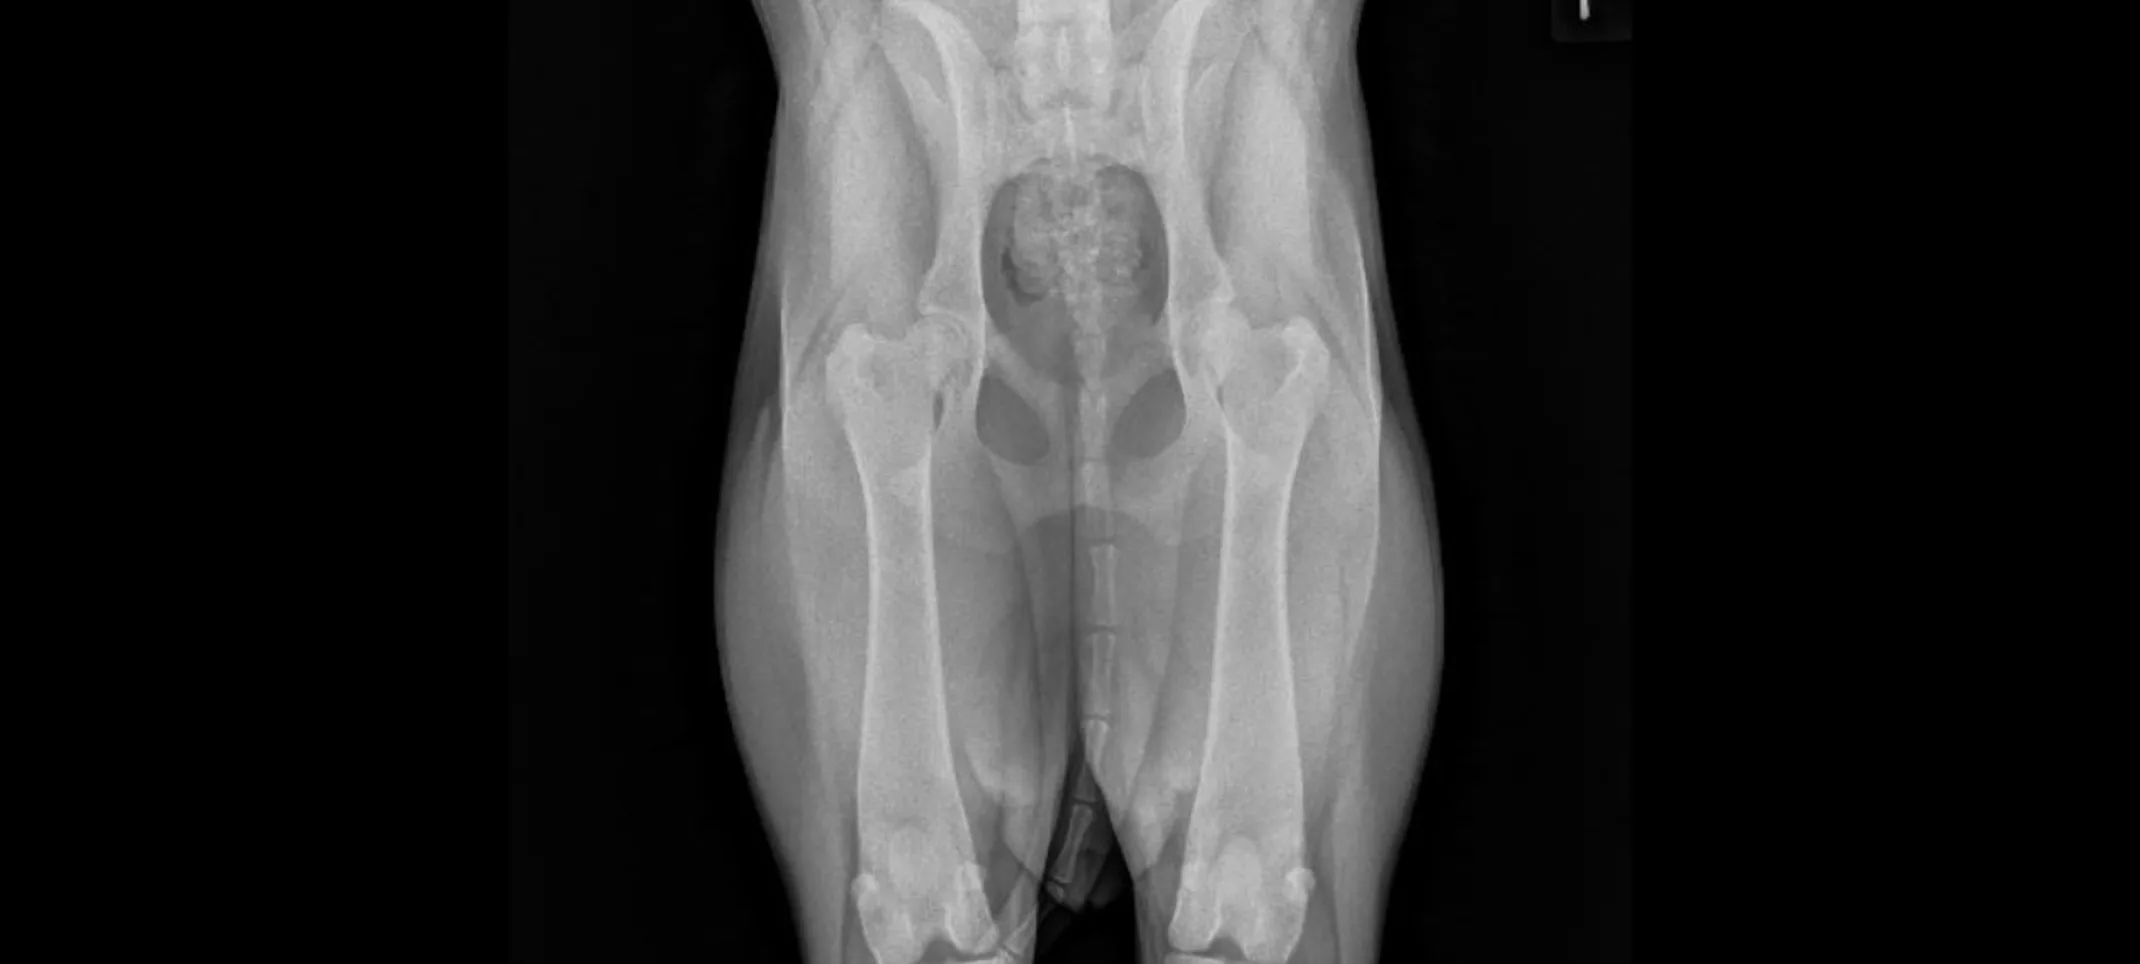

OFA certification involves evaluating radiographs (x-rays) and genetic tests to assess an animal's health for various conditions, such as hip dysplasia, elbow dysplasia, and others. This information is used by breeders to make informed decisions about breeding, aiming to produce healthier puppies and kittens.

Hips/Elbows